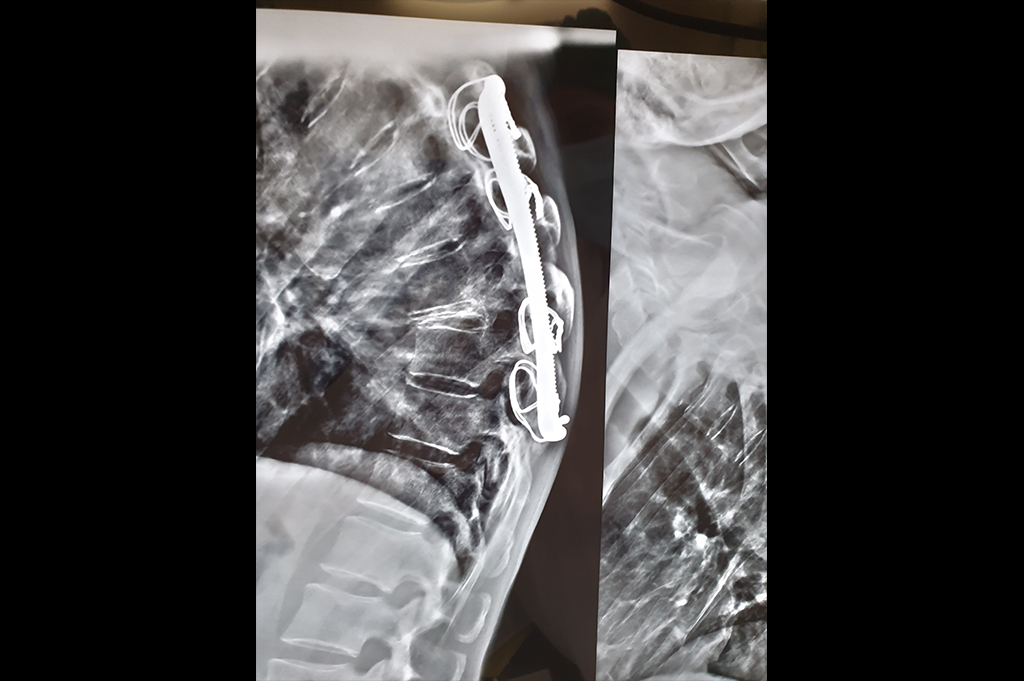

Spine